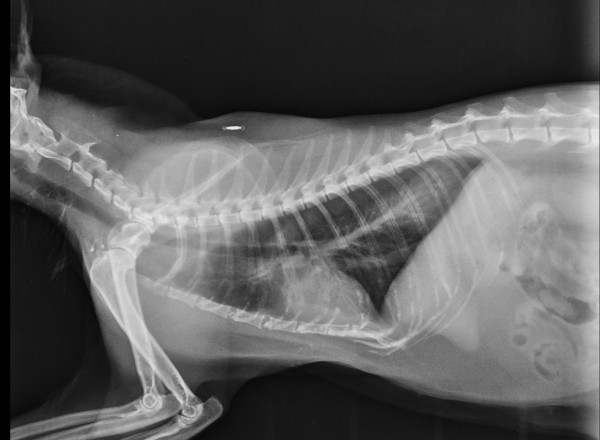

Radiographie Numérique

Radiographie Numérique Sedecal Vet

avec ou sans sédation , suivi radiologique ,